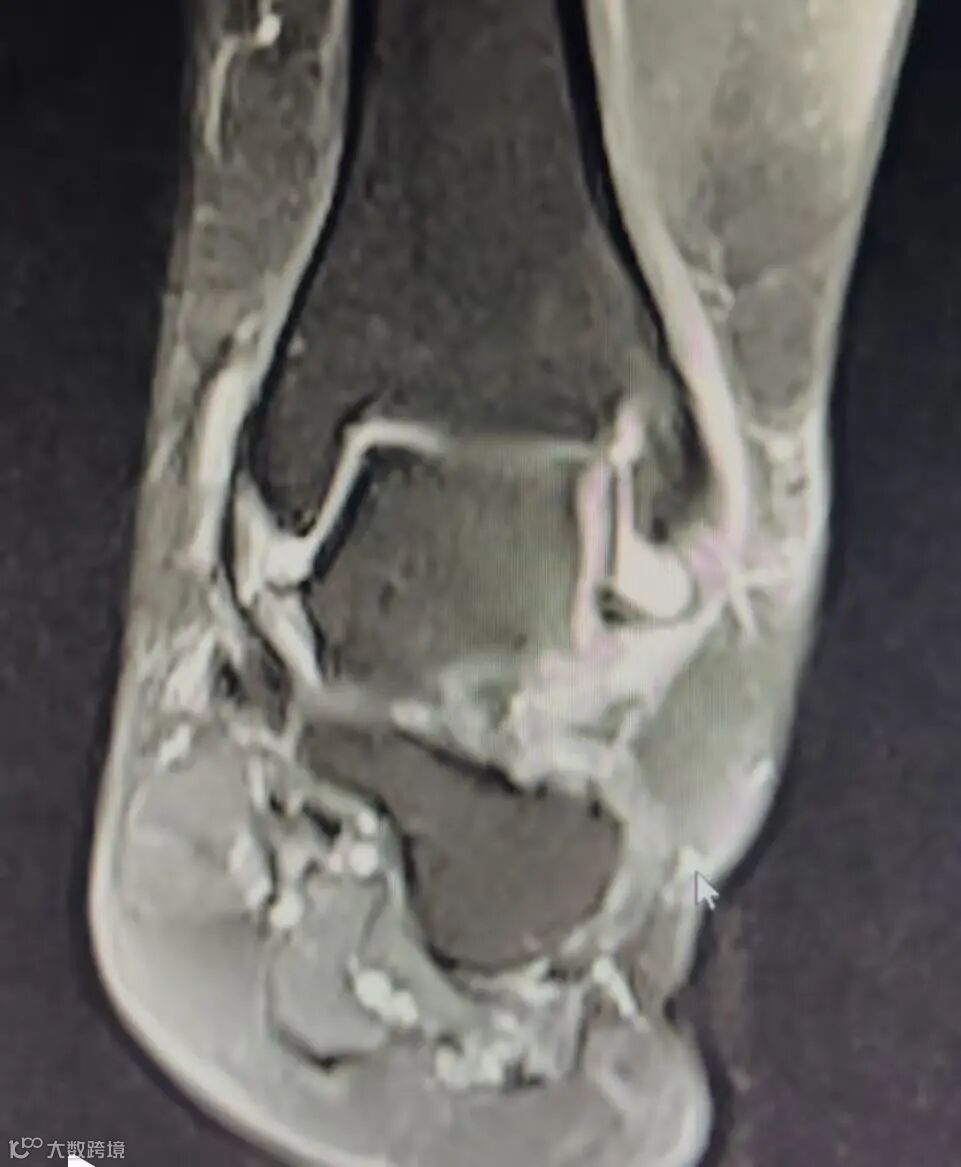

3. Arthroscopic synovectomy was performed on patients with standard portals. Anterolaterally localized hypertrophic synovitis and scar tissue were observed and debrided. In order to exclude MI, a clinical anterior drawer and/or talar tilt tests were conducted. Incombination with the stress fluoroscopy, where there was markedly a symmetricanterior laxity of the talocrural joint (5 mm), an open lateral stabilization procedure was performed and excluded. Furthermore, preoperative magnetic resonance imaging (MRI) scans were reviewed in order to document the intact or attenuated anterior talofibular ligament (ATFL) and hypertrophic synovitis. Functional instability and MI are two possible causes of CAI. Although mechanical and functional instability may occur in isolation, when combined they may contribute to CAI. MI is referred to as an increased flexibility and joint laxity and is usually attributed to damage to the ligaments of the ankle. After repetitive ankle sprains, individuals may develop chronic instability demonstrating laxity and MI. Some individuals with chronic ankle instability may present proprioceptive deficit, muscular weakness, impaired balance control, and increased neuromuscular reaction time, leading to FI. Diminished range of motion was thought to be a predisposing factor for lateral ankle sprains; indeed, many authors have shown that a dorsiflexion deficit creates a tendency toward hypersupination in CAI patients.